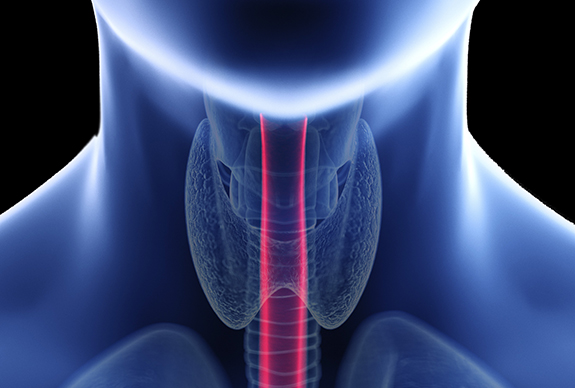

연하장애(삼킴장애)

연하장애는 삼킴에 관여하는 구상, 인두강, 후두강 이나 식도관 등의 구조 자체에 결함이 있거나 기능장애가 있을 경우에 저작과 삼키는 능력의 손실·손상으로 먹는 능력이 저하된 것으로 모든 연령층에서 나타날 수 있고 특히 고령층에서 흔히 나타납니다. 침이나 음식물을 흘린다던지 심키기를 어려워하는 모든 것이 앉은 자세, 고개의 방향, 턱의 움직임, 혀의 움직임과 감각 인두, 후두의 기능 등 여러 가지 복합적인 요소에 의해 영향을 받는 것이므로 객관적이며 정확한 평가와 작업 치료사에 의한 연하장애 치료를 하고 있습니다.

연하장애 전기자극치료(Vital Stim)